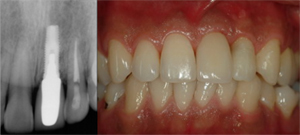

임플란트 단일치아 보철물 : 하나의 임플란트를 식립하여 하나의 치아를 수복합니다.

수술 후에는 임플란트가 뼈와 잘 붙어 고정되도록 기다리는 치유 기간이 필요합니다. 얼마나 기다려야 하는가는 경우마다 다릅니다. 수술 직후부터 임플란트가 뼈와 단단히 고정되어 있고 기타 여건이 좋을 경우에는 치유 기간을 생략하고 곧바로 보철 단계로 진행할 수도 있는 반면, 잘 고정되지 않았을 경우 뼈가 자라나 잘 고정되도록 수 주일에서 수 개월의 치유기간이 필요하게 됩니다. 뼈가 부족하여 골이식을 함께 행한 경우에는 추가로 치유 기간이 더 필요할 수 있습니다. 치유 기간 동안 치유 상태의 확인을 위해 1-2개월에 1회 정도의 내원이 필요합니다.

보철 단계는 식립된 임플란트 위에 치아 구조물을 올리는 과정입니다. 임플란트가 뼈와 잘 고정되었다고 판단된 이후에 진행합니다. 치료 규모에 따라 차이가 있을 수 있으나, 대략 1주 1회의 내원을 기준으로 1-2개월의 기간이 필요합니다.